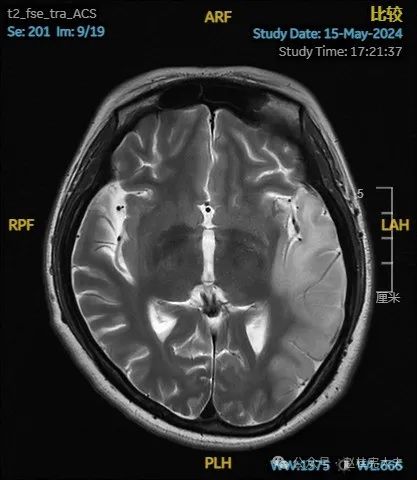

入院后给予精氨酸,左卡尼丁,辅酶Q10,维生素E等治疗。患者病情稳定好转中,2天后意识清楚,语言表达仍欠佳。当天复查颅脑磁共振如下:

以上为患者发病后3次的颅脑磁共振片子,临床诊断基本上可以确认了,希望患者逐渐恢复!